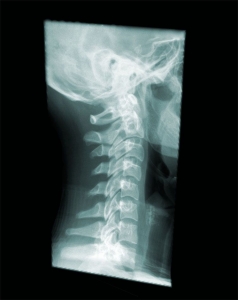

交通事故での後遺障害が認められるためには、その症状と事故との因果関係が大切になってきます。特にむち打ちは、レントゲンやMRIでも自覚症状を裏付ける他覚所見が得られないことが一般的です。従って、ご本人が事故直後からどのような症状を訴え「続けて」いるかどうかが、身体の状態を考える大事な資料となります。ご自身の訴え、すなわち自覚症状に連続性・一貫性が認められない場合、後遺障害が認定されることはまずありません。